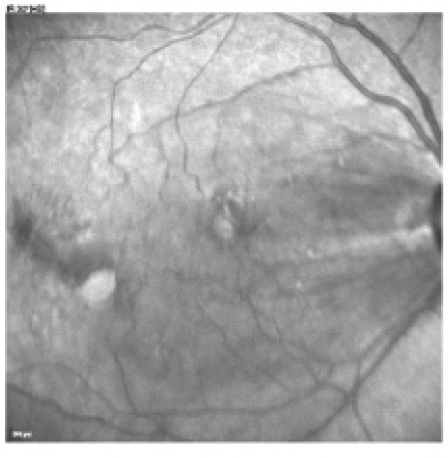

Figure 1. Preoperative infrared reflectance (A), blue autofluorescence (B), blue reflectance (C), and infrared autofluorescence (D) images demonstrating the ERM.

Funduscopic examination revealed an ERM that distorted the macular anatomy (Figure 1). Spectral-domain optical coherence tomography (SD-OCT) imaging of her right macula confirmed the presence of the ERM (Figure 2).